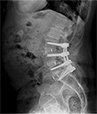

Patient Cases After picAfter

• Patient Reviews before image case 2After Surgery